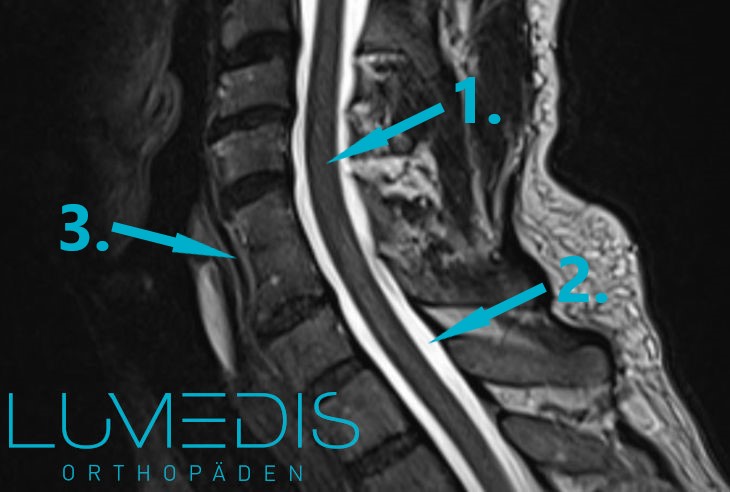

MRT Blockwirbel C5/C6 in der HWS

Ein MRT wird häufig bei einer Cervicobrachialgie durchgeführt, da die häufigste Ursache der Cervicobrachialgie der Bandscheibenvorfall der HWS ist.

Dieser wird standardmäßig durch das MRT diagnostiziert, da hier die Strukturen der Bandscheiben am besten und am präzisesten zu beurteilen sind.

Daher wird ein MRT immer dann durchgeführt, sobald ein begründeter Verdacht auf einen Bandscheibenvorfall in der Halswirbelsäule vorliegt.

Weitere Informationen finden Sie im Artikel Magnetresonanztomographie der Halswirbelsäule.

MRT einers Bandscheibenvorfalls der HWS (seitliche T2 Aufnahme):